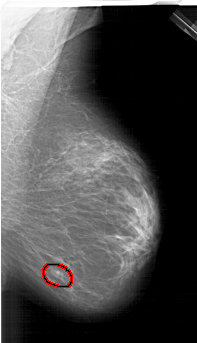

RIGHT_MLO LINES 6166 PIXELS_PER_LINE 3541 BITS_PER_PIXEL 12 RESOLUTION 43.5 OVERLAY